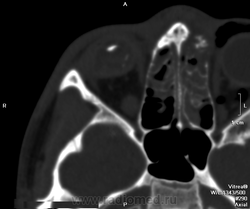

Постарайтесь все-таки раздобыть анамнез. Скорее всего травма в анамнезе или воспаление. Глазное яблоко уменьшено в размерах, деформировано с массивными кальцинатами, стекловидное тело уплотнено. Это называется Phtisis Bulbi. Как по русски, не знаю. Вроде как атрофия или субатрофия.

http://www.radpod.org/2008/04/02/phthisis-bulbi/

Вот здесь есть одна картинка http://www.radiomed.ru/publications/orbitalnaya-patologiya-perevod-nela